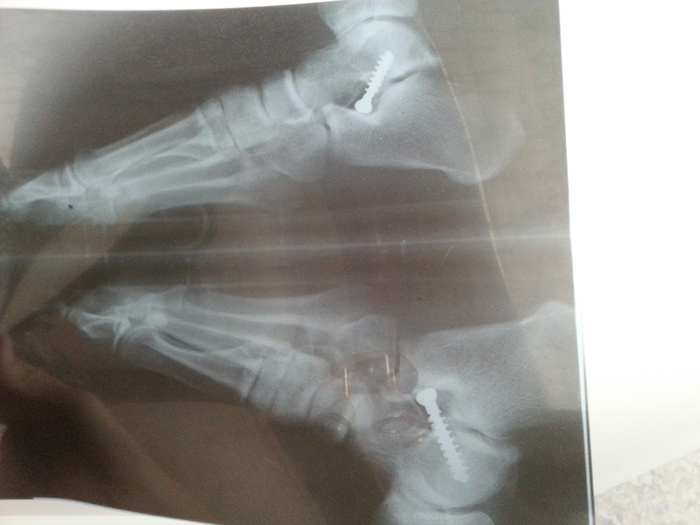

Когда стукнуло 21 год, я повторно сделал обследование в своем родном городе в ортопедическом центре и в этот раз сказали, что есть операция КЛАПС, которую можно сделать пока ты молод, она безопасно, срок восстановления около месяца, суть в том, что в стопы вкручивают винты и со временем плоскостопие исправляется. Потом их убирают (года через 2-3). Если не сделать, в старости может возникнуть артроз стоп.

Фотографии ниже - это уже спустя полгода и рентген снимок с "винтами".